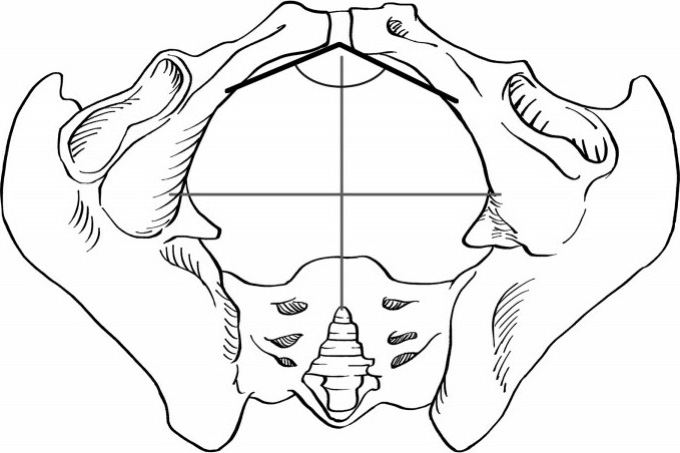

骨盆是由骶骨、尾骨和左右两块髋骨围成的环状骨骼及其形成的骨盆腔组成。以骨盆入口平面为界将骨盆腔分为上下两部分,上部分为假骨盆、下部分为真骨盆(图2.1)。骨产道特指真骨盆,是阴道分娩时胎儿必经的骨性通道。

图2.1 真骨盆与假骨盆

真骨盆有三个具有产科意义的假想平面,即骨盆入口平面、中骨盆平面和骨盆出口平面。这三个平面的形态及大小与胎头的相对位置是评估胎儿能否通过骨产道的关键(图2.2)。

图2.2 骨盆三个平面